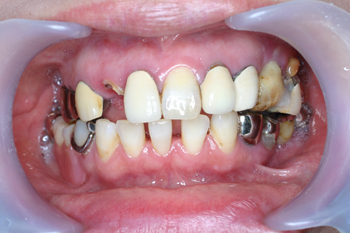

歯がボロボロになる原因は、大きく分けて虫歯・歯周病の2つです。どちらも普遍的な症状ですが、治療方法が全く違います。

ボロボロの歯でも残せる歯が多い場合、詰め物や被せ物での治療が可能な場合もあります。保険診療での治療が可能ですが、歯の状態によっては抜歯せざるを得ない場合もあります。

綺麗な見た目にしたり、金属以外の被せ物で治療をしたい場合は自由診療となりますが、患者様のご要望に合わせて治療方法をお選びいただけます。